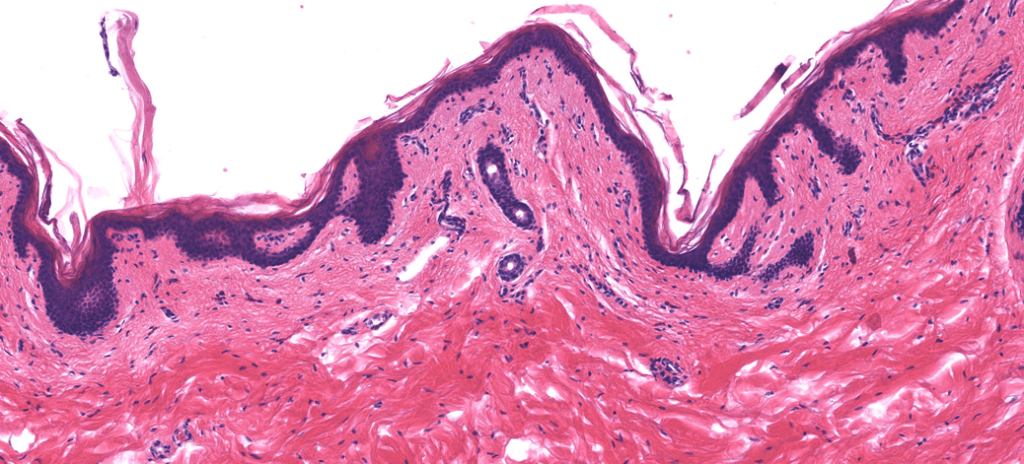

TEJIDO CONJUNTIVO DENSO (TCD)

Forma la cápsula de algunos órganos y se ubica sobre todo en la Dermis reticular. Contiene pocas células y muchas fibras.

REGULAR: fibras con dirección y orientación.

IRREGULAR: fibras dispersas, sin dirección específica.